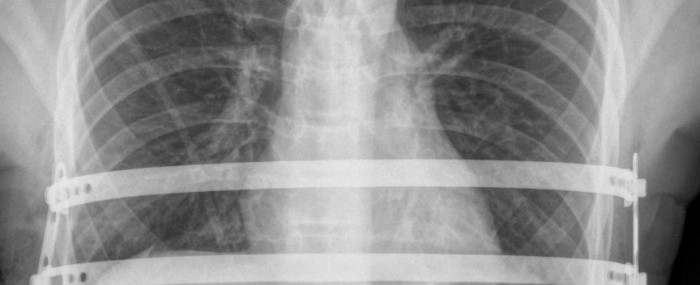

Roseli Andrion | Pesquisa para Inovação – Na rotina de atendimentos no Instituto do Coração (Incor) da Faculdade de Medicina da Universidade de São Paulo (USP), o cirurgião torácico Miguel Tedde costuma se deparar com casos de pacientes com uma doença rara, chamada pectus excavatum (peito escavado, em latim). A condição causa a compressão do coração e do pulmão, além de alterações psicológicas, e seu tratamento consiste na implantação de próteses metálicas moldadas por trás do osso esterno (também conhecido como “osso do peito”) para empurrá-lo para a frente. O dispositivo usado para essa finalidade, contudo, é importado e apresenta problemas, como o fato de ser feito de um material não biocompatível – o aço – e ter o risco de deslocamento.

A única correção efetiva é cirúrgica: implantam-se próteses metálicas moldadas por trás do esterno para empurrá-lo para a frente. Antes do desenvolvimento do implante nacional, utilizava-se uma opção importada feita de aço inox com extremidades serrilhadas e dois estabilizadores para fixação — só que nem sempre os estabilizadores eram efetivos e as barras podiam se deslocar e comprimir estruturas mediastinais, como o coração ou grandes vasos. “Esse deslocamento é um perigo.”

O implante brasileiro é feito de titânio, um elemento química e biologicamente mais compatível com o corpo humano — o que reduz a ocorrência de reações alérgicas. Além disso, as barras têm as extremidades lisas e os estabilizadores têm posicionamento oblíquo e parafusos de pressão para fixação. Isso rendeu uma patente. “Juntei boas ideias com soluções já validadas para criar uma melhor, que garantisse mais segurança ao procedimento”, conta Tedde.

As correções são feitas por videotoracoscopia, uma técnica minimamente invasiva, e a incisão, que antigamente era frontal, passou a ser medial e, agora, é lateral. Com o uso dos implantes nacionais, foi possível, ainda, reduzir o tempo de internação após o procedimento. Entre os 30 primeiros pacientes do projeto, esse período caiu de sete para cinco dias. Já para os 20 seguintes, o tempo no hospital limitou-se a quatro dias.